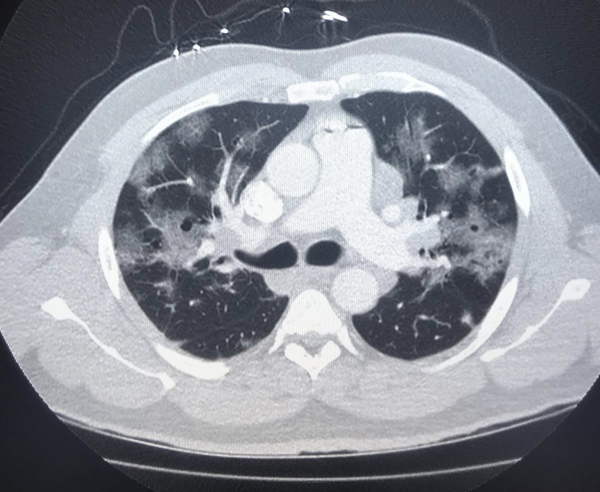

“The role of CT and cardiology in COVID-19 is still very much to be learned in the midst of this pandemic,” explained Society of Cardiovascular CT (SCCT) Vice President Ed Nicol, M.D., MBA, FSCCT, Royal Brompton and Chelsea and Westminster Hospitals, London, who offered an overview of the key takeaways at the SCCT 2020 meeting closing session. However, he said CT has emerged as one of the primary imaging modalities in the COVID era. The latest technical advances and trends in CT and the latest clinical study data were discussed at the SCCT 2020 virtual meeting in July.

He noted CT can be used to evaluate chest pain, etiology of LV dysfunction, new onset of heart failure or cardiomyopathy, evaluation of patients with possible angina and new arrhythmias. And, unlike echocardiography, it does not require clinicians to be in close proximity to patients being scanned. CT exams are also fast, helping reduce the exposure time spent with patients.